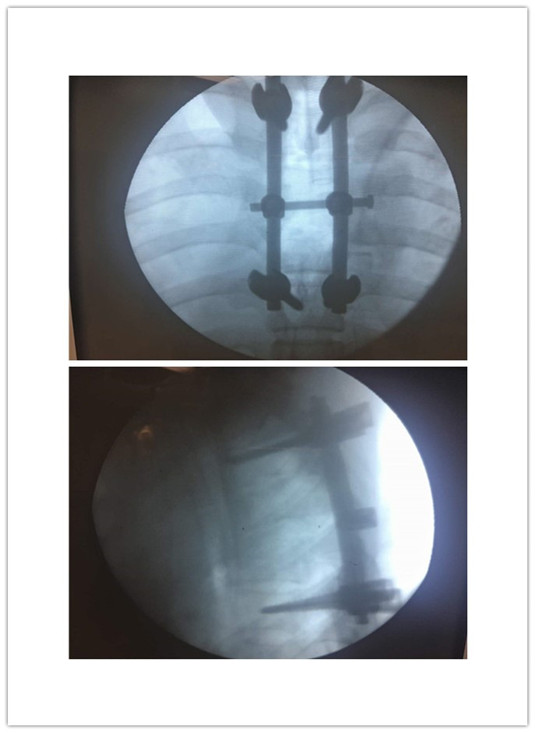

在陈月明主任亲自主刀下,装钉固定、骨折复位、脊髓松解……经过大家4个多小时的奋战,夜里近2:00手术终于顺利完成。患者入院时病情危重已经截瘫,幸运的是通过大家的努力,年轻的生命得到了延续……